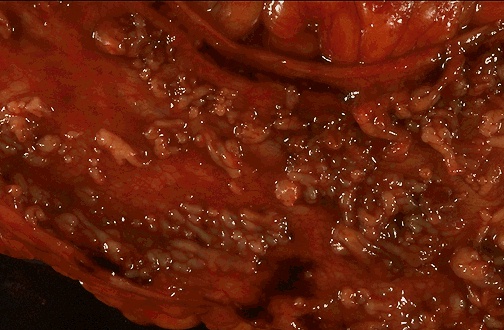

Pseudopolyps are seen here in a case of severe ulcerative colitis. The remaining mucosa has been ulcerated away and is hyperemic. A colonoscopic view of active ulcerative colitis, but not so eroded as to produce pseudopolyps, is seen below